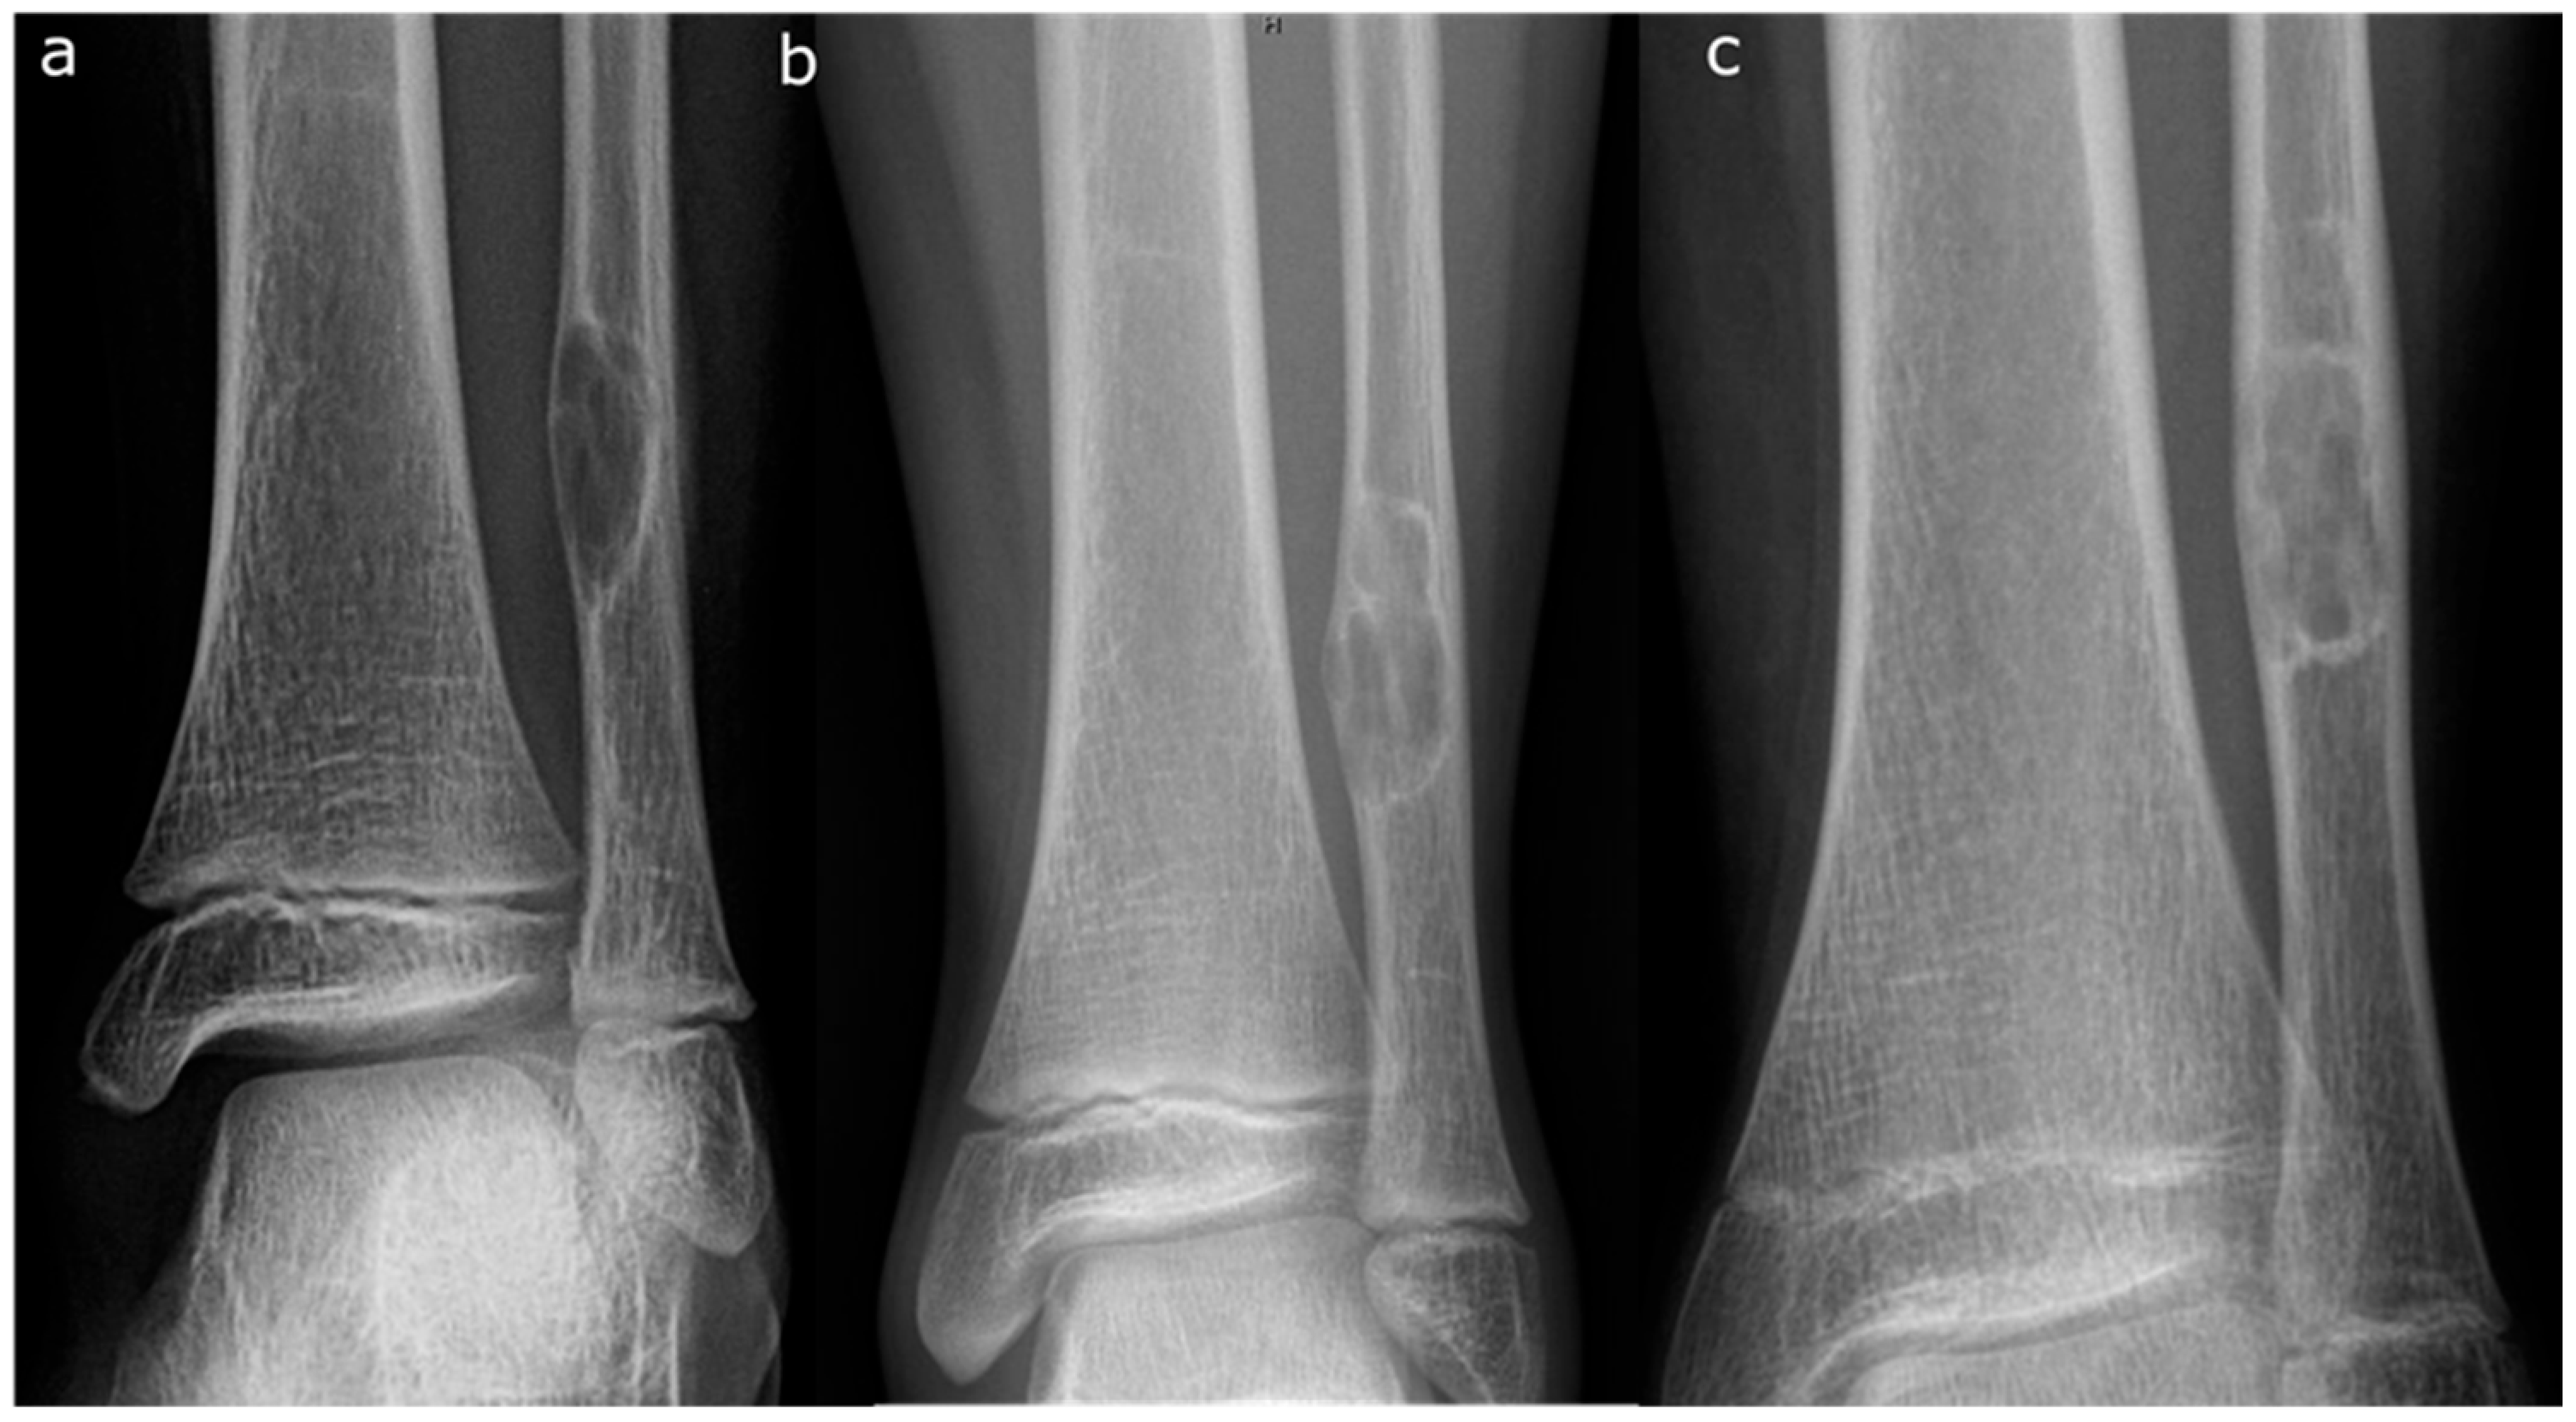

- Pac-Man Sign—Proliferation of bone anterior and posterior to the syndesmosis results in a shape that resembles the video game character “Pac-Man”. This sign was found to be highly specific (95%) but not very sensitive (47%) for predicting pathologic fracture (Figure 3).

- Computed Tomography (CT): CT can be useful for evaluating the degree of cortical thinning, which is important when assessing fracture risk [24]. CT is superior for delineating the precise cortical integrity. It allows for quantitative measurement of the cross-sectional area occupied by the lesion, which is a key factor in biomechanical models predicting fracture risk. The signs described above can also be visualized on a CT scan. Figure 3 demonstrates a “Pac-Man Sign” on CT of a 13-year-old boy who had a fracture through an NOF.